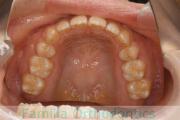

八重歯を治したいということで来院されました。下あごの左ずれのある上顎前突(出っ歯)・叢生(でこぼこ)でしたので、上は左右から、下はで左のみ小臼歯を抜歯して、歯科矯正用アンカースクリューとマルチブラケット法にて治療を行いました。2年強、30回程度の通院が必要でした。

上下とも前歯の叢生(でこぼこ、凹凸、ガタガタ)があるため、保定を怠ると後戻りのリスクがあります。

上顎

下顎